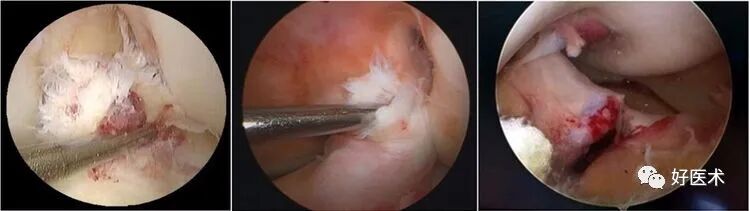

6)假瘤:

韧带损伤后断端较整齐,残端组织增生并被滑膜包裹呈“瘤状”,如果突出于前方为“独眼征”。

多见于韧带股骨附着部撕裂及部分撕裂。